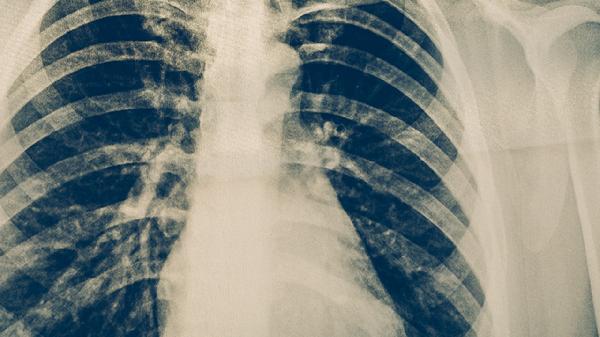

出现持续咳嗽、低热、盗汗等可疑症状时,应立即进行胸部X线检查和痰液检测。确诊患者应严格遵医嘱完成全程抗结核治疗,不可擅自停药。对密切接触者开展预防性筛查,早期发现潜伏感染可采用药物预防干预。